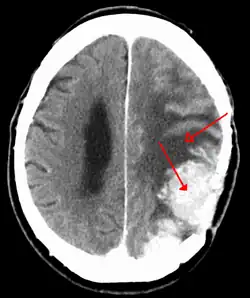

Meningiomas are visualized readily with contrast CT, MRI with gadolinium,[23] and arteriography, all attributed to the fact that meningiomas are extra-axial and vascularized. CSF protein levels are usually found to be elevated when lumbar puncture is used to obtain spinal fluid. On T1-weighted contrast-enhanced MRI, they may show a typical dural tail sign absent in some rare forms of meningiomas.[18]